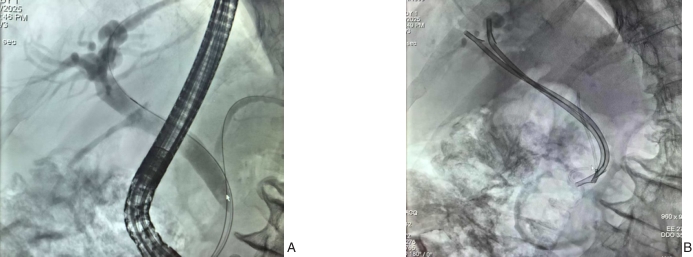

图1 病例3术中资料 A:ERCP造影显示胆汁漏瘘口位置(近腹壁处);B:ERCP技术胆道内置入2根内支架引流管Fig.1